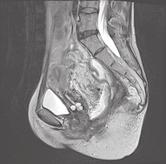

Pacientka narozená v roce 1988 trpěla od roku 2008 ulcerózní kolitidou s extenzivním postižením tlustého střeva. Od doby stanovení diagnózy byla léčena kombinovanou konvenční terapií mesalazinem, systémovými kortikoidy a imunosupresivy (azathioprin), aniž bylo dosaženo trvalejší remise. Pro chronicky aktivní průběh choroby byla ošetřujícím gastroenterologem indikována k provedení proktokolektomie s vytvořením ileopouch-anální anastomózy. Výkon byl proveden v roce 2016 otevřeným přístupem ve dvou dobách. V první fázi byla provedena proktokolektomie s formováním J pouche a ileopouch-anální anastomózy s pojistnou ileostomií v květnu 2016. Výkon byl komplikován traumatem stěny vaginy s nutností její sutury. V resekátu tlustého střeva byly zjištěny těžké zánětlivé a pozánětlivé změny, tubulizace lumen střeva a stenóza sigmatu v délce 20cm. V několika histologických řezech byly zachyceny shluky aktivovaných makrofágů, které byly hodnoceny jako mikrogranulomy. Pro přetrvávající subfebrilie a noční poty bylo koncem května 2016 provedeno CT vyšetření, při němž byla verifikována presakrální abscesová kolekce velikosti 55 × 45 mm. Následně byla provedena drenáž abscesu radiologicky pod CT kontrolou s velmi dobrým klinickým efektem.

S odstupem několika měsíců byla v září 2016 zrušena pojistná ileostomie a obnovena střevní kontinuita. Po stabilizaci stavu měla pacientka 5–8 stolic denně, měla intermitentní bolesti v podbřišku, vyprazdňovala střevní obsah z pouche bez hnisu, krve nebo hlenu, v noci byla zpravidla 1–2krát probuzena pro potřebu vyprázdnění střevního obsahu. Celkově se cítila velmi unavená, občasně měla zvýšené teploty a noční poty. Užívala intermitentně topické i systémové kortikosteroidy, mesalazin a opakovaně metronidazol, celkově a lokálně v podobě čípků. Několikrát byla provedena endoskopie ileálního J-pouche, při kterých byl zjištěn nález ojedinělých a spíše povrchových vředů, vždy v distální části pouche nad vytvořenou pouch-anální anastomózou. V průběhu dalších ně-

kolika let postupně ztrácela na tělesné hmotnosti. Mezi lety 2017 a 2024 zhubla celkem o 12kg, nejnižší hmotnost měla v první polovině roku 2024, a to 37 kg (BMI = 16). V červenci 2024 byla provedena pouchoskopie s překvapujícím nálezem píštěle lokalizované cca 35 mm nad ileopouch-anální anastomózou na zadní cirkumferenci, o průměru cca 3–4mm (viz video, které naleznete na webu www.csgh.info). Následně byla doplněna MR malé pánve (obrázky). Jaká je vaše diagnóza? A jaký bude další terapeutický postup?

Otázka:

Jaká je Vaše diagnóza? Správnou odpov a komentá naleznete v p íštím ísle.